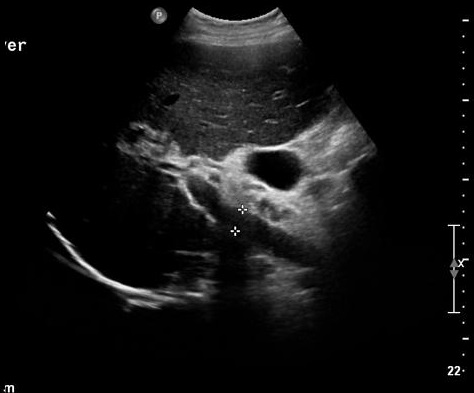

Stade de hypertension portale

d'une cirrhose biliaire du foie ,

complication d'une cholangite slerosant

primitive de voie biliaire . Dans ce coupe

la veine port est tres distendue 13,5mm ( <

11mm en normalement ) foie est

hypoechogene et rude |